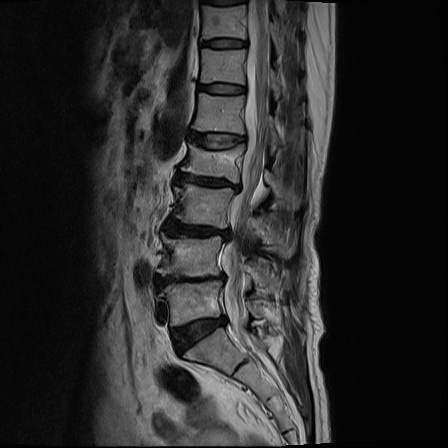

Ӵϲ ɿ ô ô 㸮 ٸ ̾ϴ. ϵ Ͻð ܻ 㸮 20⵿ ͽϴ. mri ˻ ɿ Ȳ ʹ ؼ Ȳ̶ ߽ϴ. ϻȰ ϰ 鼭 ½ϴ. ̴ ø鼭 Ͻô Ȳ ̷ ġ ص ȸ ϴ. δ Ҵµ, ù ȸԲ ˷ֽ ϰ β ϰ, ˷ֽ ü ƮĪ ϸ鼭 ȭǸ鼭 Ӵϲ ȸų ְ ǰ, β 鼭 ʴ β ؾϴ ŷο 1ϸ ijħ ڸ ǥ Ʈ ߽ϴ. ȸ ȭϽø鼭 Ϸ簡 ٸ ȸǽð 4ְ Ǿ Ǯ鼭 ¦ ҽϴ. ħ ȸ ȭϸ鼭 ڼ ü ƮĪ ϴ. ȥڼ Ͻʴϴ. ٳø鼭 ó Ͻ ʴϴ. ̾ ְ ̳ ߵ ʰ ϴ ȸԲ Ͻʴϴ. ʹ ϸ鼭 ϴ. Ȩ - ϱ ٴ Ȳ MRIԴϴ. |